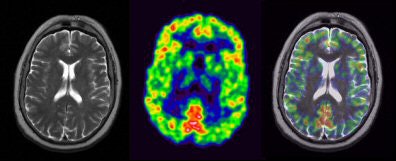

![]() |

| FLAIR, ADC, T1 MPRAGE, and T2 TSE were applied during the same PET acquisition. PET shows absence of FDG signal from pathological periventricular regions. Images courtesy of Bernd Pichler, Ph.D., and colleagues at the University of Tübingen and David Townsend, Ph.D., and colleagues the University of Tennessee. |

| Comparative brain images with diffusion echoplanar imaging sequence applied during PET acquisition. Images courtesy of Bernd Pichler, Ph.D., and colleagues at the University of Tübingen and David Townsend, Ph.D., and colleagues at the University of Tennessee. |